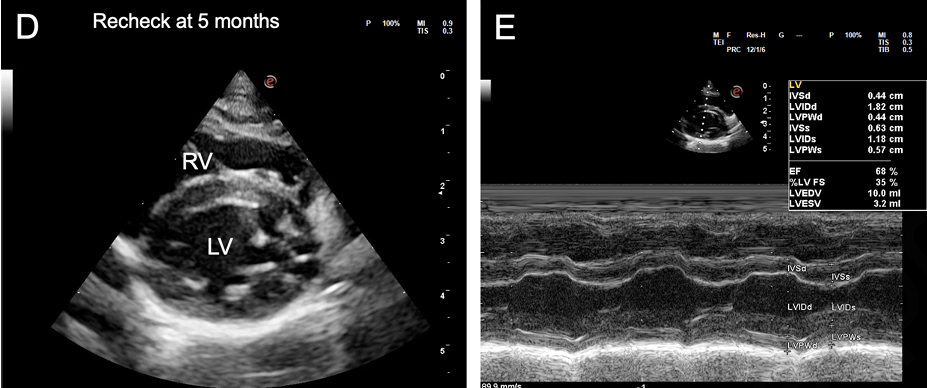

- 치료 후 심장 기능의 회복: 심부전 치료와 항생제 치료를 시작한 후, 2.5개월, 5개월, 9개월 차에 진행된 추적 심장 초음파 검사에서 놀라운 변화가 관찰되었습니다. 확장되었던 심방과 심실의 크기가 정상 범위로 줄어들고, 저하되었던 심실 수축 기능 또한 정상으로 회복되는 '역 리모델링(reverse remodeling)'이 명확하게 확인되었습니다.